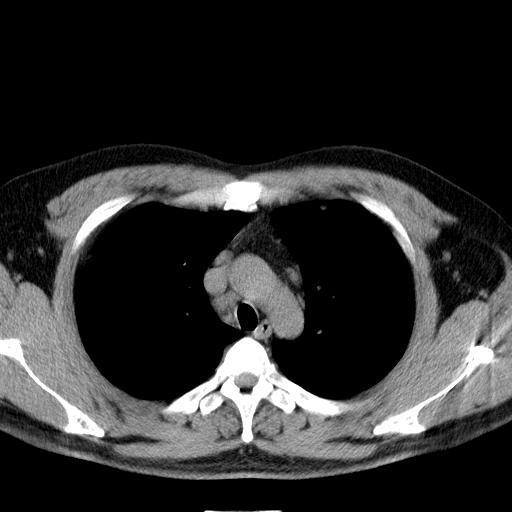

双肺多发散在结节影,部分边界不清,延支气管分布;纵隔内多发小结节(淋巴结)影...

考虑

1.双肺转移ca及纵隔淋巴结转移;

2.特殊类型感染(霉菌)?

3.韦氏肉芽肿?